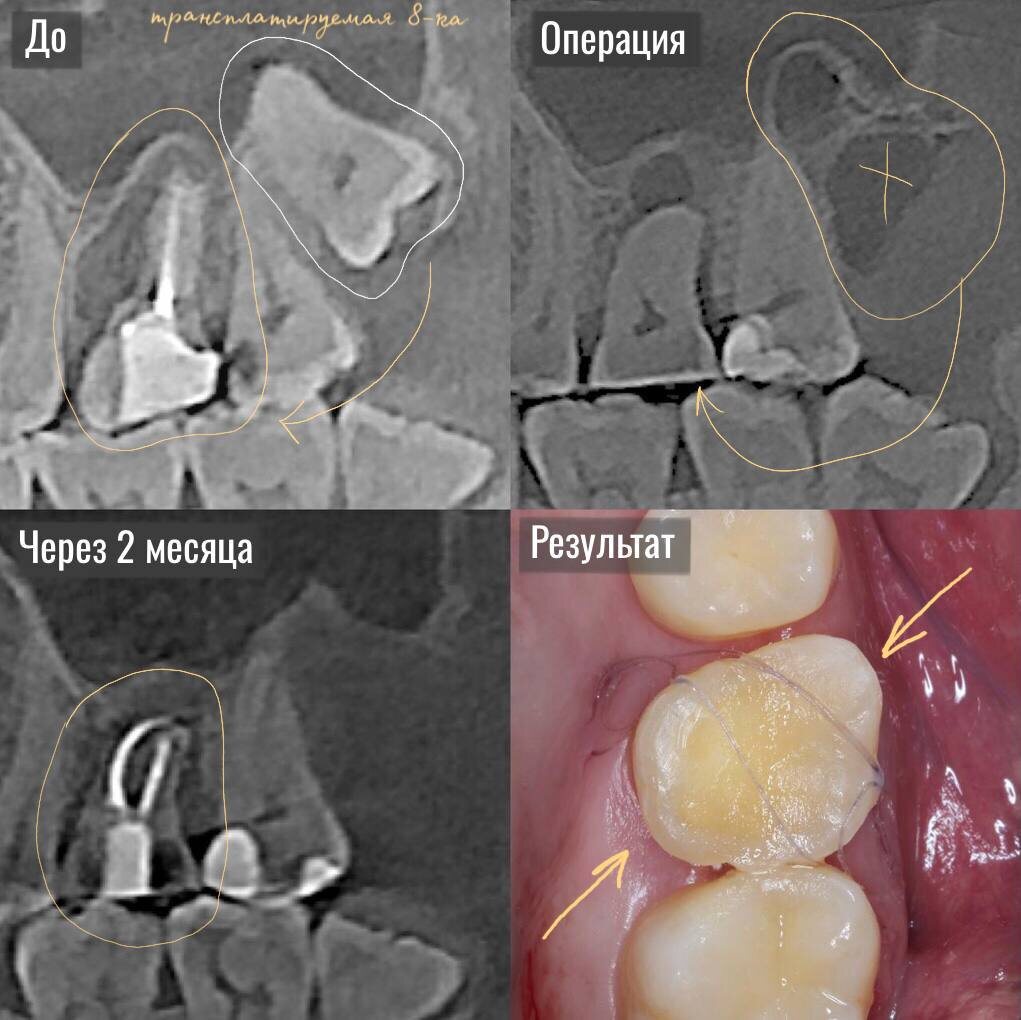

На фото представлена работа наших врачей.  Представьте: у вас разрушена 6ка, а в прикусе есть абсолютно здоровая, но бесполезная (так как не в прикусе) 8ка (зуб мудрости).  Вместо того чтобы удалять ее «в никуда», мы можем пересадить ее на место утраченного зуба! Да, это не миф — это аутотрансплантация. Когда аутотрансплантация оправдана? Процедура подходит не всем, но в ряде случаев это отличная альтернатива имплантации. Она возможна, если: — есть здоровый зуб мудрости или премоляр, который не участвует в жевании и фактически бесполезен в прикусе; — корни зуба относительно прямые (желательно одни корень); — форма зуба соответствует удаляемому.  В некоторых случаях предварительно изготавливается 3D модель пересаживаемого зуба для примерки и коррекции лунки. Почему не имплантат? Метод подходит не всем и требует строгих показаний, но у него есть свои весомые плюсы: — Подходит, когда противопоказана имплантация. — Вокруг своего зуба лучше восстанавливается десна и лучше прилегает к

Процедура аутотрансплантации в данном случае была выполнена за один визит:

Доктор провел максимально атравматичное удаление 6ки (так как ее нельзя было пролечить) с сохранением целостности лунки.

Сразу же на место удаленного зуба был помещен зуб-донор — 8ка. Ее скорректировали по высоте и зафиксировали швами.

Через две недели у "нового" зуба были пролечены каналы и произведена подготовка для установки искусственной коронки.

А через 2 месяца — контрольное КЛКТ, на котором видны признаки восстановления костной ткани.